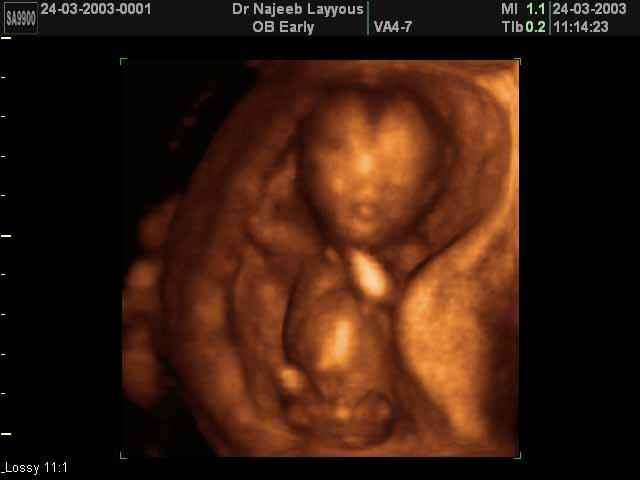

- 3D Photos Ecographie du Premier Trimestre